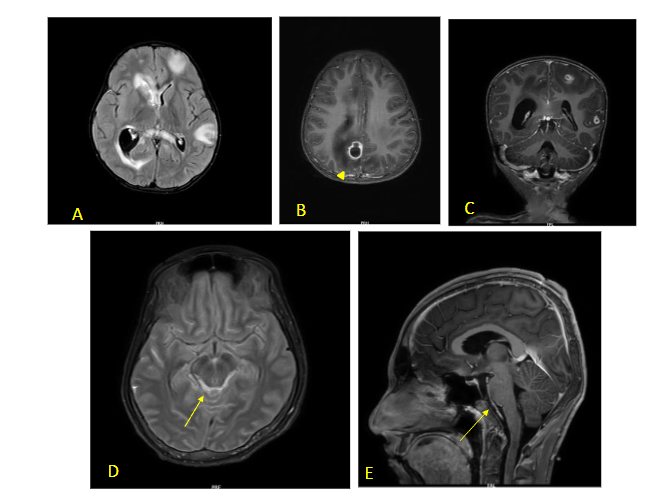

FIRES is usually associated with normal imaging at the outset. Some cases show swelling in the mesial temporal or hippocampal regions presumably from prolonged seizure activity. Late scans show diffuse cortical atrophy due to a combination of brain injury and use of prolonged steroids.

FIG 6 A–D: Fever induced refractory epilepsy syndrome (FIRES) – 8-year-old with onset of refractory seizures on Day 7 of febrile illness. Initial MRI (T2/FLAIR) images are normal (A,B). Subsequent scan done 10 days later showed diffusion restriction in left peri-Rolandic area – arrow (C,D). EEG showed persistent electrical seizures in left > right occipital regions which responded well to Midazolam and Ketamine infusion along with ketogenic diet.